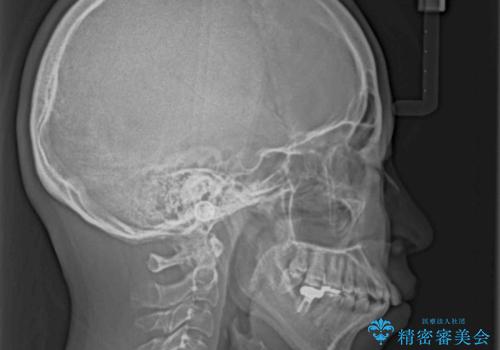

- 上下の出っ歯を気にして来院された患者様です。

口元を積極的に引っ込めるために、上下左右の第一小臼歯を4本抜歯することとしました。

また、上下前歯は舌の突出癖による開咬となっていたため、舌のトレーニングを徹底するよう指示しました。